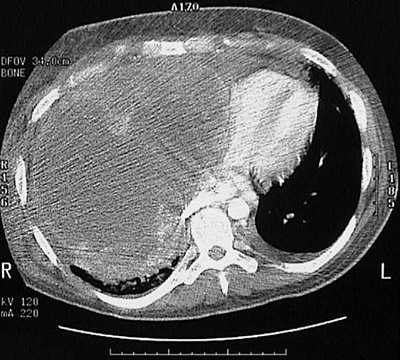

This large mass that nearly fills the right chest cavity is an angiosarcoma arising in the epicardium adjacent to the right ventricle of the heart.